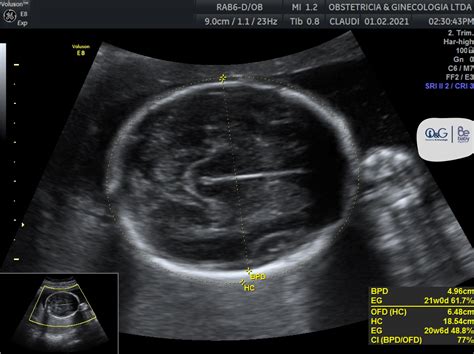

- Diámetro biparietal (DBP): Representa la distancia entre los dos lados de la cabeza del bebé, medida a la altura del tálamo. Esta medida es una buena referencia del crecimiento fetal.

- Circunferencia de la cabeza (CC): Corresponde a la circunferencia de la cabeza del bebé.

Durante la ecografía, el técnico utilizará un transductor para enviar y recibir ondas sonoras que rebotan en el bebé, creando una imagen en una pantalla. Adicionalmente, la ecografía Doppler proporciona información sobre las características del flujo sanguíneo a través de los vasos, siendo la arteria umbilical y la arteria cerebral media los vasos más estudiados para el control del bienestar fetal. La ecografía 2D permite observar la placenta, diferenciando una placenta joven y en buen estado de una placenta envejecida, que puede presentar calcificaciones y cambios de textura.